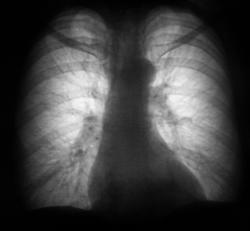

Сложилось впечатление, что имеет место ателектаз верхней доли справа. Посмотрели имеющийся архив за 2007, 2008 годы.

Забрали пациентку в рентгенодиагностический кабинет.

Выяснили, что 4 месяца тому пациентка упала с лестница, "было очень больно", но за медицинской помощью не обращалась.

Действительно не обычно смотрится. При ограниченном пневмотораксе границы обычно вогнутые, а не выпуклые, но другого варианта у меня тоже нет - локальный пневмоторакс.

Такая картина развивается при длительно существующем пневмотораксе или пневмогидротораксе: на висцеральной плевре образуется фибрин, формируются спайки между висцеральной и париетальной плеврой, фиксирующие легкое, что не позволяет ему расправиться.

"формируются спайки между висцеральной и париетальной плеврой, фиксирующие легкое, что не позволяет ему расправиться."

Или повторно коллабироваться полностью - спайки "поддержат" - почти шутка.